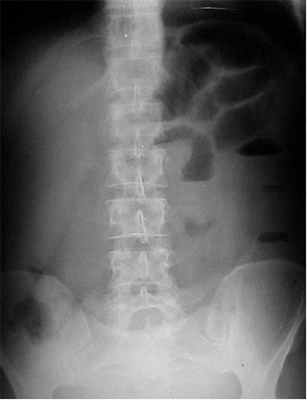

Прямая обзорная рентгенография брюшной полости в вертикальном положении демонстрирует значительное расширение петель кишечника и уровни жидкости в них. Чем больше петель визуализируется, тем ниже располагается препятствие.

На рентгенограммах, полученных в положении стоя или лежа на боку, обычно видны горизонтальные уровни жидкости и газа (рис. 2). Рисунок 2. Обзорная рентгенограмма брюшной полости. Видны чаши Клойбера, уровни жидкости. Заполненные газом кишечные петли имеют вид опрокинутых чаш (чаши Клойбера). Они появляются при странгуляции через 1-2 ч после начала заболевания, при обтурации - через 3-5 ч. По размерам чаш Клойбера, их форме и локализации можно судить об уровне непроходимости.

При тонкокишечной непроходимости чаши Клойбера небольших размеров, ширина горизонтального уровня жидкости больше, чем высота столба газа над ним. Обычно наблюдается большое количество горизонтальных уровней с изменением их расположения в течение времени и перемещением жидкости из одной петли в другую. Горизонтальные уровни жидкости ровные. На фоне газа хорошо видны складки слизистой оболочки (складки Керкринга), принимающие форму растянутой спирали.

При непроходимости тощей кишки горизонтальные уровни жидкости локализуются в левом подреберье и эпигастральной области. При непроходимости в терминальном отделе подвздошной кишки уровни жидкости расположены в области мезогастрия.

При тонкокишечной непроходимости, кроме чаш Клойбера, на рентгенограммах видны растянутые газом кишечные петли, принимающие форму «аркад» или «органных труб», похожих на перевернутые буквы J и U.